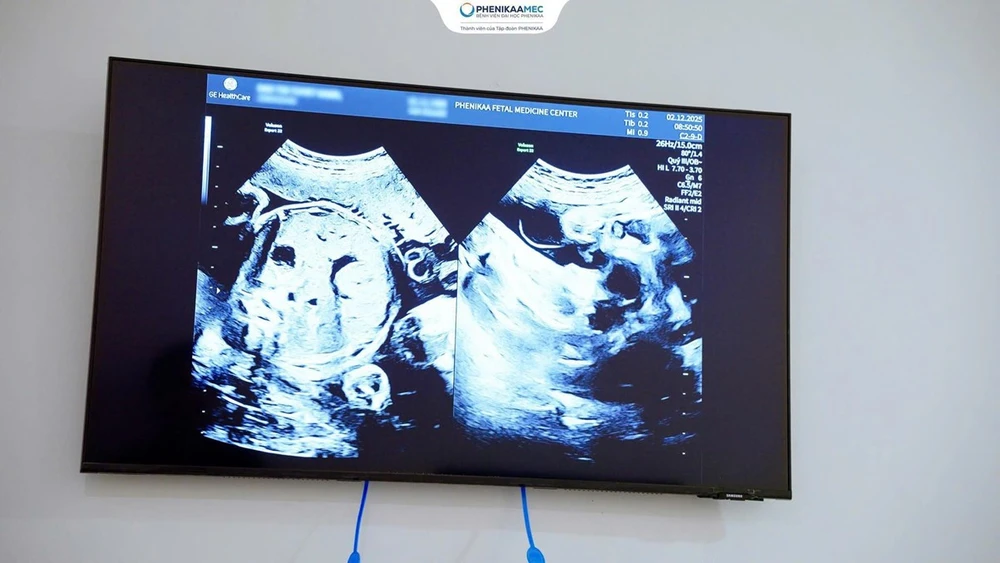

Ngay từ những tuần đầu thai kỳ, sản phụ T.H. được TS. BS Nguyễn Thị Sim (Giám đốc Trung tâm Y học Bào thai PhenikaaMec) trực tiếp theo dõi và xây dựng kế hoạch quản lý cá thể hóa. Thai phụ được áp dụng các tiêu chuẩn theo dõi quốc tế với siêu âm hình thái và đánh giá tăng trưởng thai theo khuyến cáo ISUOG (Hiệp hội Siêu âm Sản Phụ khoa Quốc tế), kết hợp theo dõi Doppler động mạch tử cung – động mạch rốn nhằm phát hiện sớm nguy cơ suy thai, tiền sản giật và sinh non.

phenikaamec-cuu-san-phu-song-thai-rau-tien-dao-ra-huyet-am-dao-o-at-o-tuan-33-sinh-con-an-toan-o-36-tuan.jpg

Sản phụ mang song thai bánh rau hai buồng ối sau 10 năm mong con.